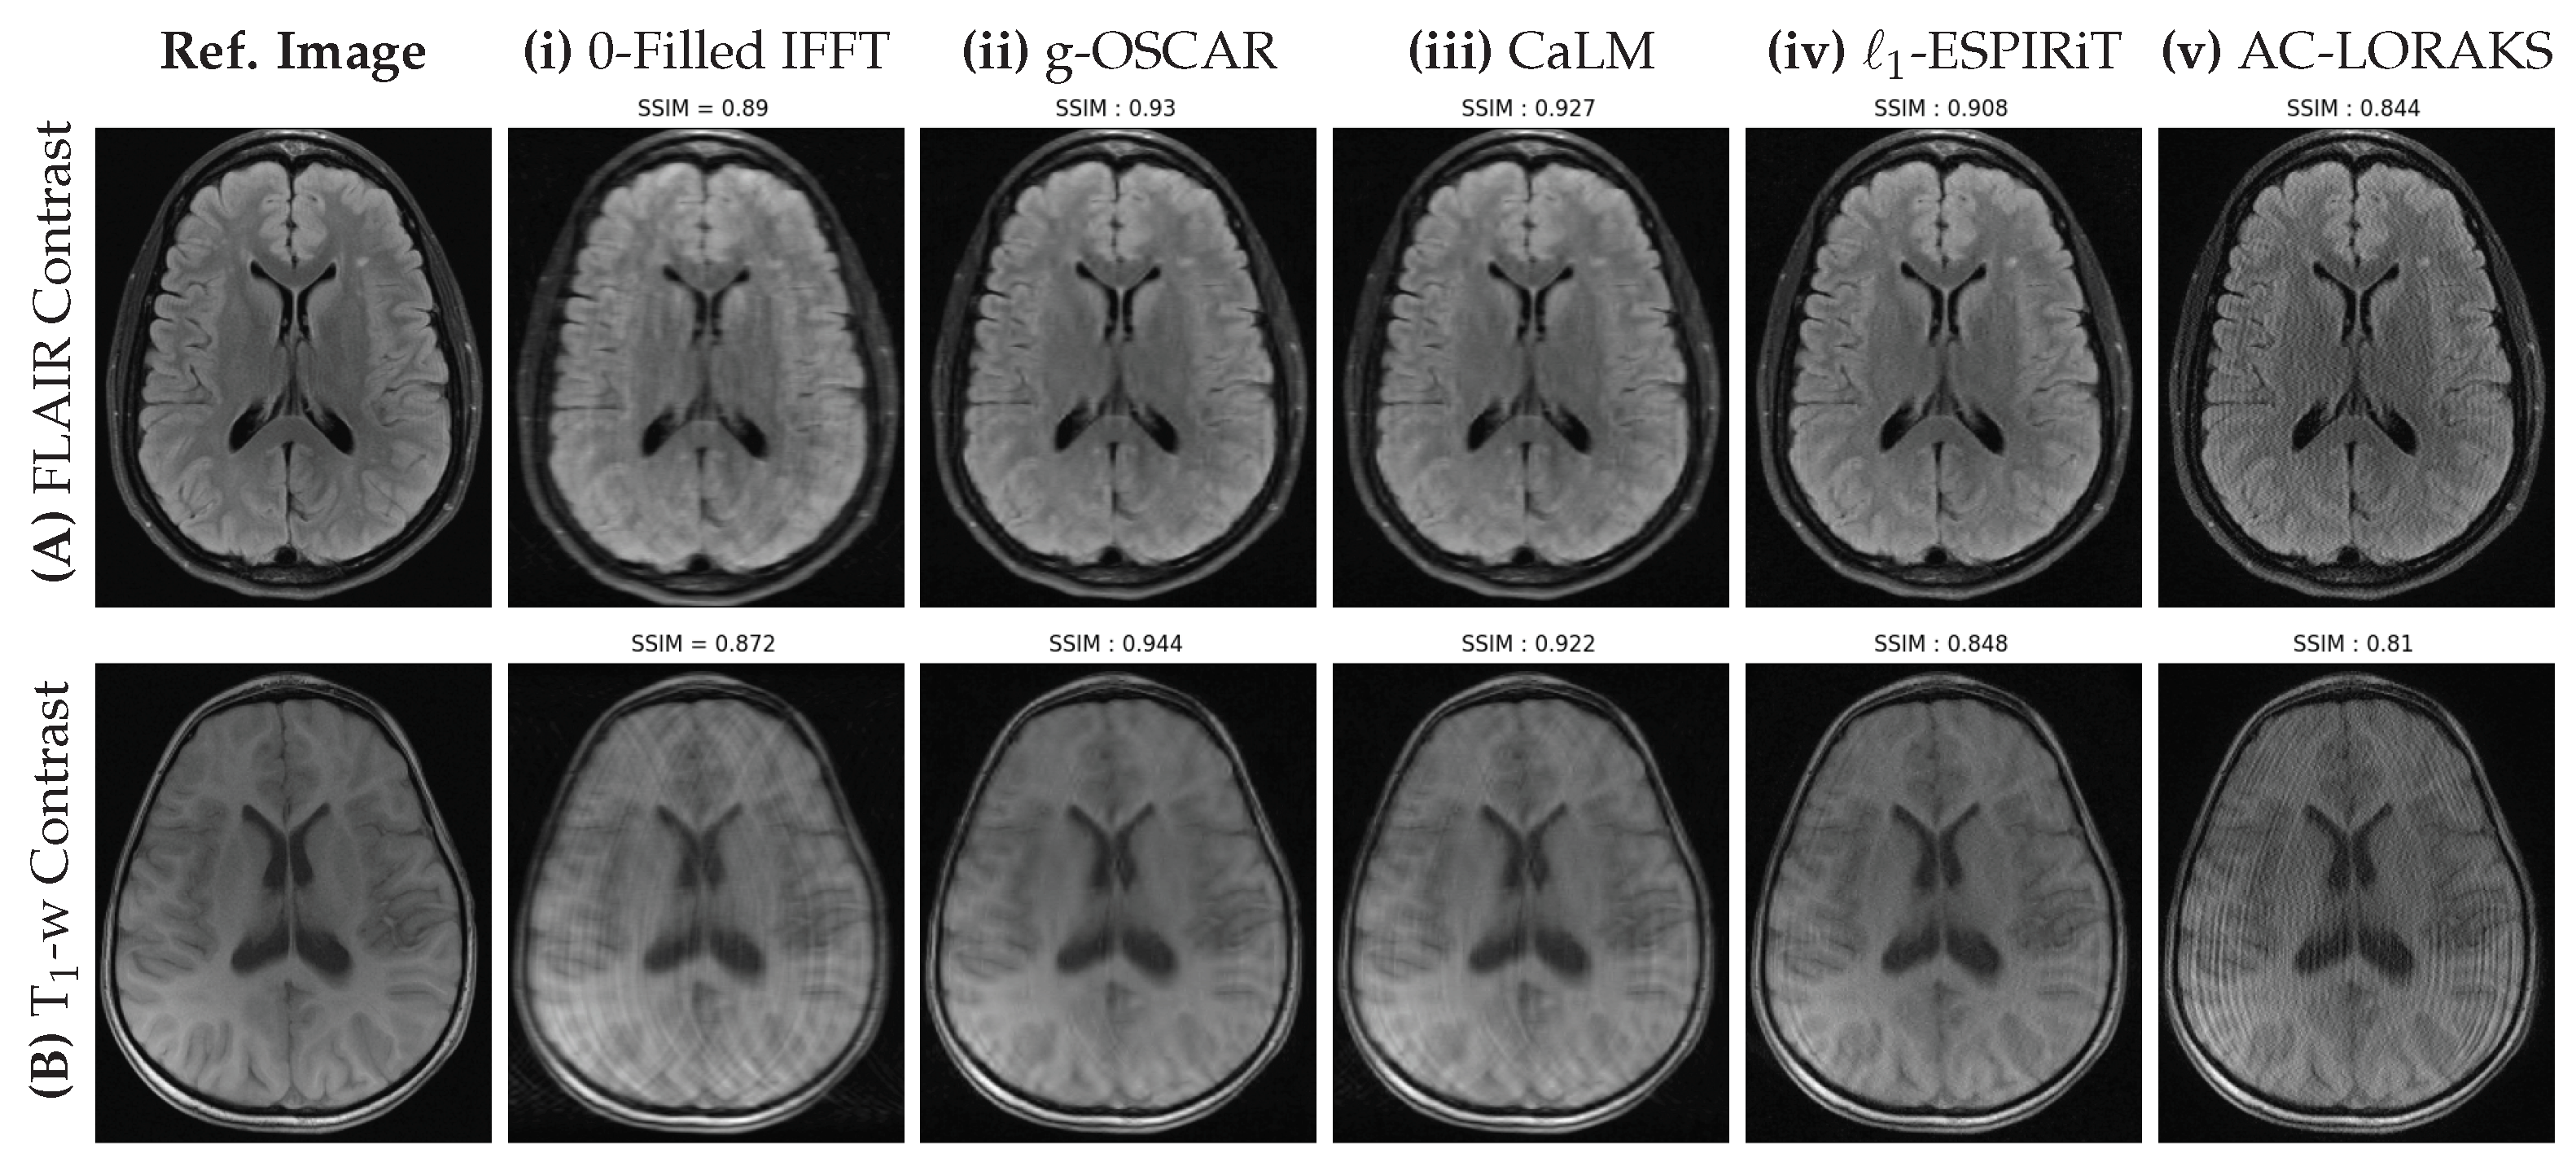

Figure 4.

Retrospective results for a single slice of FLAIR (top row) and T1 weighted (bottom row) images of the brain fastMRI data set obtained using the Cartesian mask shown in Figure 3A with , corresponding to . The fully sampled Cartesian reference and the different methods (Zero filled Inverse, g-OSCAR, CaLM, L1-ESPiRIT and AC-LORAKS) are shown from left to right and the SSIM scores are indicated to reflect the performance of each method.

Interestingly, in the retrospective Cartesian sampling scenario (cf. Figure 4), all methods perform better on the FLAIR contrast in comparison with the T1-weighted images which show severe aliasing artifacts. The zero-filled IFFT solution is severely blurred for both imaging contrasts. On top of the well visible artifacts on the L1-ESPiRIT and AC-LORAKS images, a loss in contrast is also observed for these methods on FLAIR images. In contrast, still on the FLAIR contrast CaLM and g-OSCAR report a limited amount of artifacts. The same under-sampling pattern appears more challenging on T1-weighting images as g-OSCAR is the only method which is capable to eradicate aliasing artifacts.